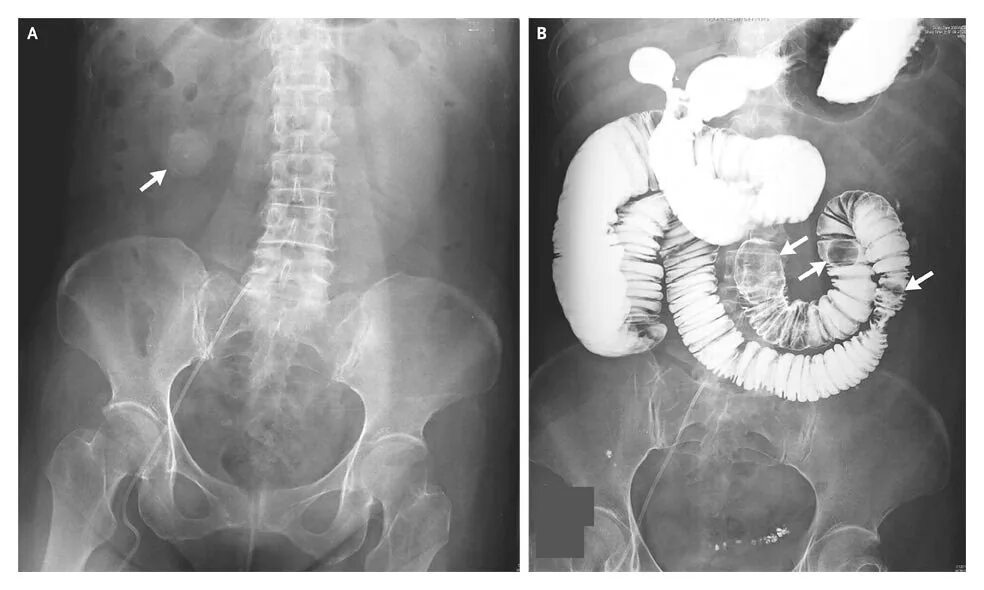

Симптом чаши